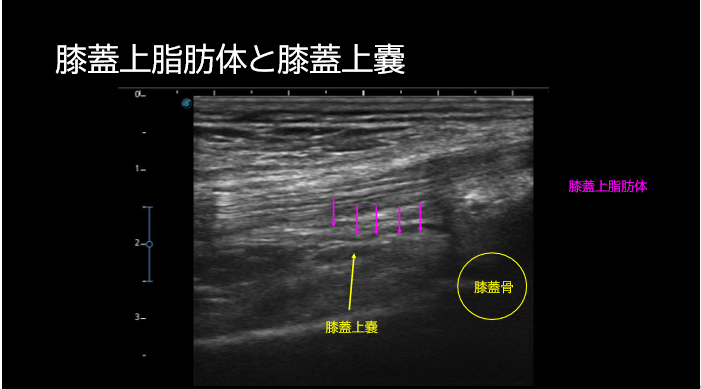

[エコー問題の解答例]

※超音波エコー評価とアプローチの選択 運動器リハに必須のエコー測定とアプローチ 下肢編では、プローブの当て方や画像の描出方法について詳しく解説します。